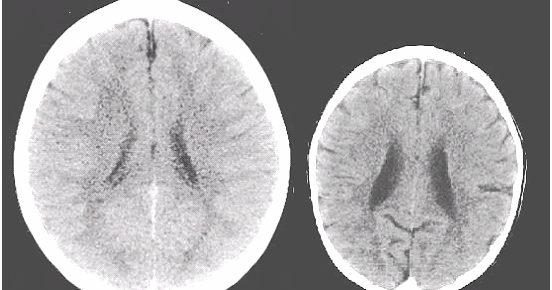

Kaspar hauser syndrome | Hyperphagic short stature: A case report and review of literature

The Kaspar Hauser Syndrome of 'Psychosocial Dwarfism'

THE KASPAR HAUSER SYNDROME OF PSYCHOSOCIAL DWARFISM | John Money | First Edition; First Printing